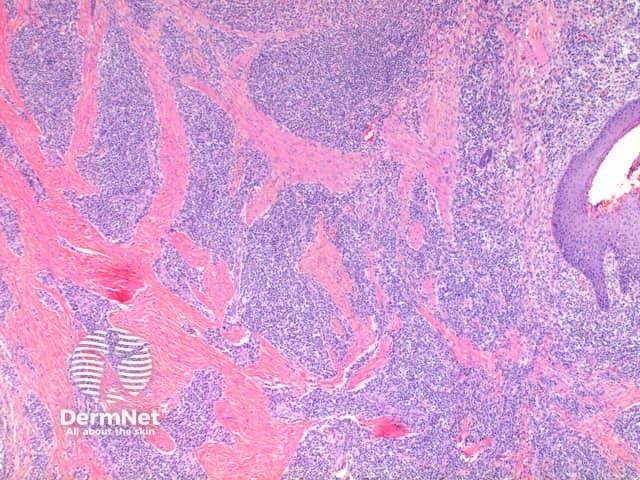

Low power view exhibits a dense superficial and deep inflammatory process with dermal scarring and follicular disruption (Figure 1). There may be variable degrees of overlying scale crust with tufted hair follicles evident as multiple hair shafts within widened follicular infundibulae (Figures 1 and 2). In the dermis are disrupted hair follicles with scattered naked hair shafts seen within a fibrotic dermis (Figures 2 and 3). There is a dense lymphoplasmacytic infiltrate with scattered neutrophils (Figure 4).

Figure 3